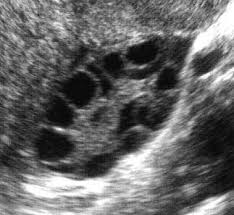

Het moment dat ik mijn gynaecoloog vertelde dat ik dacht PCO(S) te hebben zei ze dat zij dat inderdaad al dacht daar ik wat voller ben. Vervolgens kreeg ik een inwendige echo en kon ik zien dat ik gelukkig wel eitjes aanmaakte, maar dat deze op de een of andere manier dus niet 'doorkomen' en er hierdoor geen menstruatie op gang komt. 'Als je geen eitjes aanmaakte was het een groter probleem' vervolgde zij. Vervolgens vertelde ze mij dat ik met afvallen wel weer mijn menstruatie op gang zou krijgen en daarna kon ik weer gaan.

Nee, dat had de gynaecoloog niet gezien of tenminste niet verteld. Wat zij zei was dat ik genoeg eitjes had en ook een normaal aantal. Na mijn echo te hebben vergeleken met echo's van vrouwen met PCOS zag ik wel een verschil: Op mijn echo zijn mijn eitjes kleine stipjes/rondjes en op de andere echo's zag ik voornamelijk veel grotere rondjes. Dit zijn cystes of vochtblaasjes, volgens mij. Zelf denk ik die niet te hebben.

https://encrypted-tbn1.gstatic.com/imag ... PUCGDMEQVA

Die eierstokken van mij zien er soortgelijk uit. Die "kralenketting" is een symptoom dat echt bij PCOS hoort, dat hoor je te zien bij de diagnose PCOS. Als je die niet ziet en er is ook geen bloedonderzoek gedaan, kun je onmogelijk die diagnose krijgen.

Overgewicht, acne, het uitblijven van de menstruatie en overbeharing horen ook bij de symptomen, maar daar kun je PCOS niet mee vaststellen, er zijn meer ziektes/afwijkingen die deze symptomen geven.

Ik zou een second opinion aanvragen(met bloedonderzoek!) om duidelijkheid te krijgen.

quote:LaFleurNoire schreef op 12 augustus 2015 @ 15:16:

Ik zou een second opinion aanvragen(met bloedonderzoek!) om duidelijkheid te krijgen.Ik heb net ook even mijn echo erbij gepakt en ik heb deze 'kralenketting' niet. Ik vind het steeds opmerkelijker worden dat er met 'zekerheid' werd vastgesteld dat ik PCO(S) heb, maar na alles zo gelezen te hebben ga ik zeker voor een second opinion mét bloedonderzoek inderdaad om meer zekerheid te krijgen!